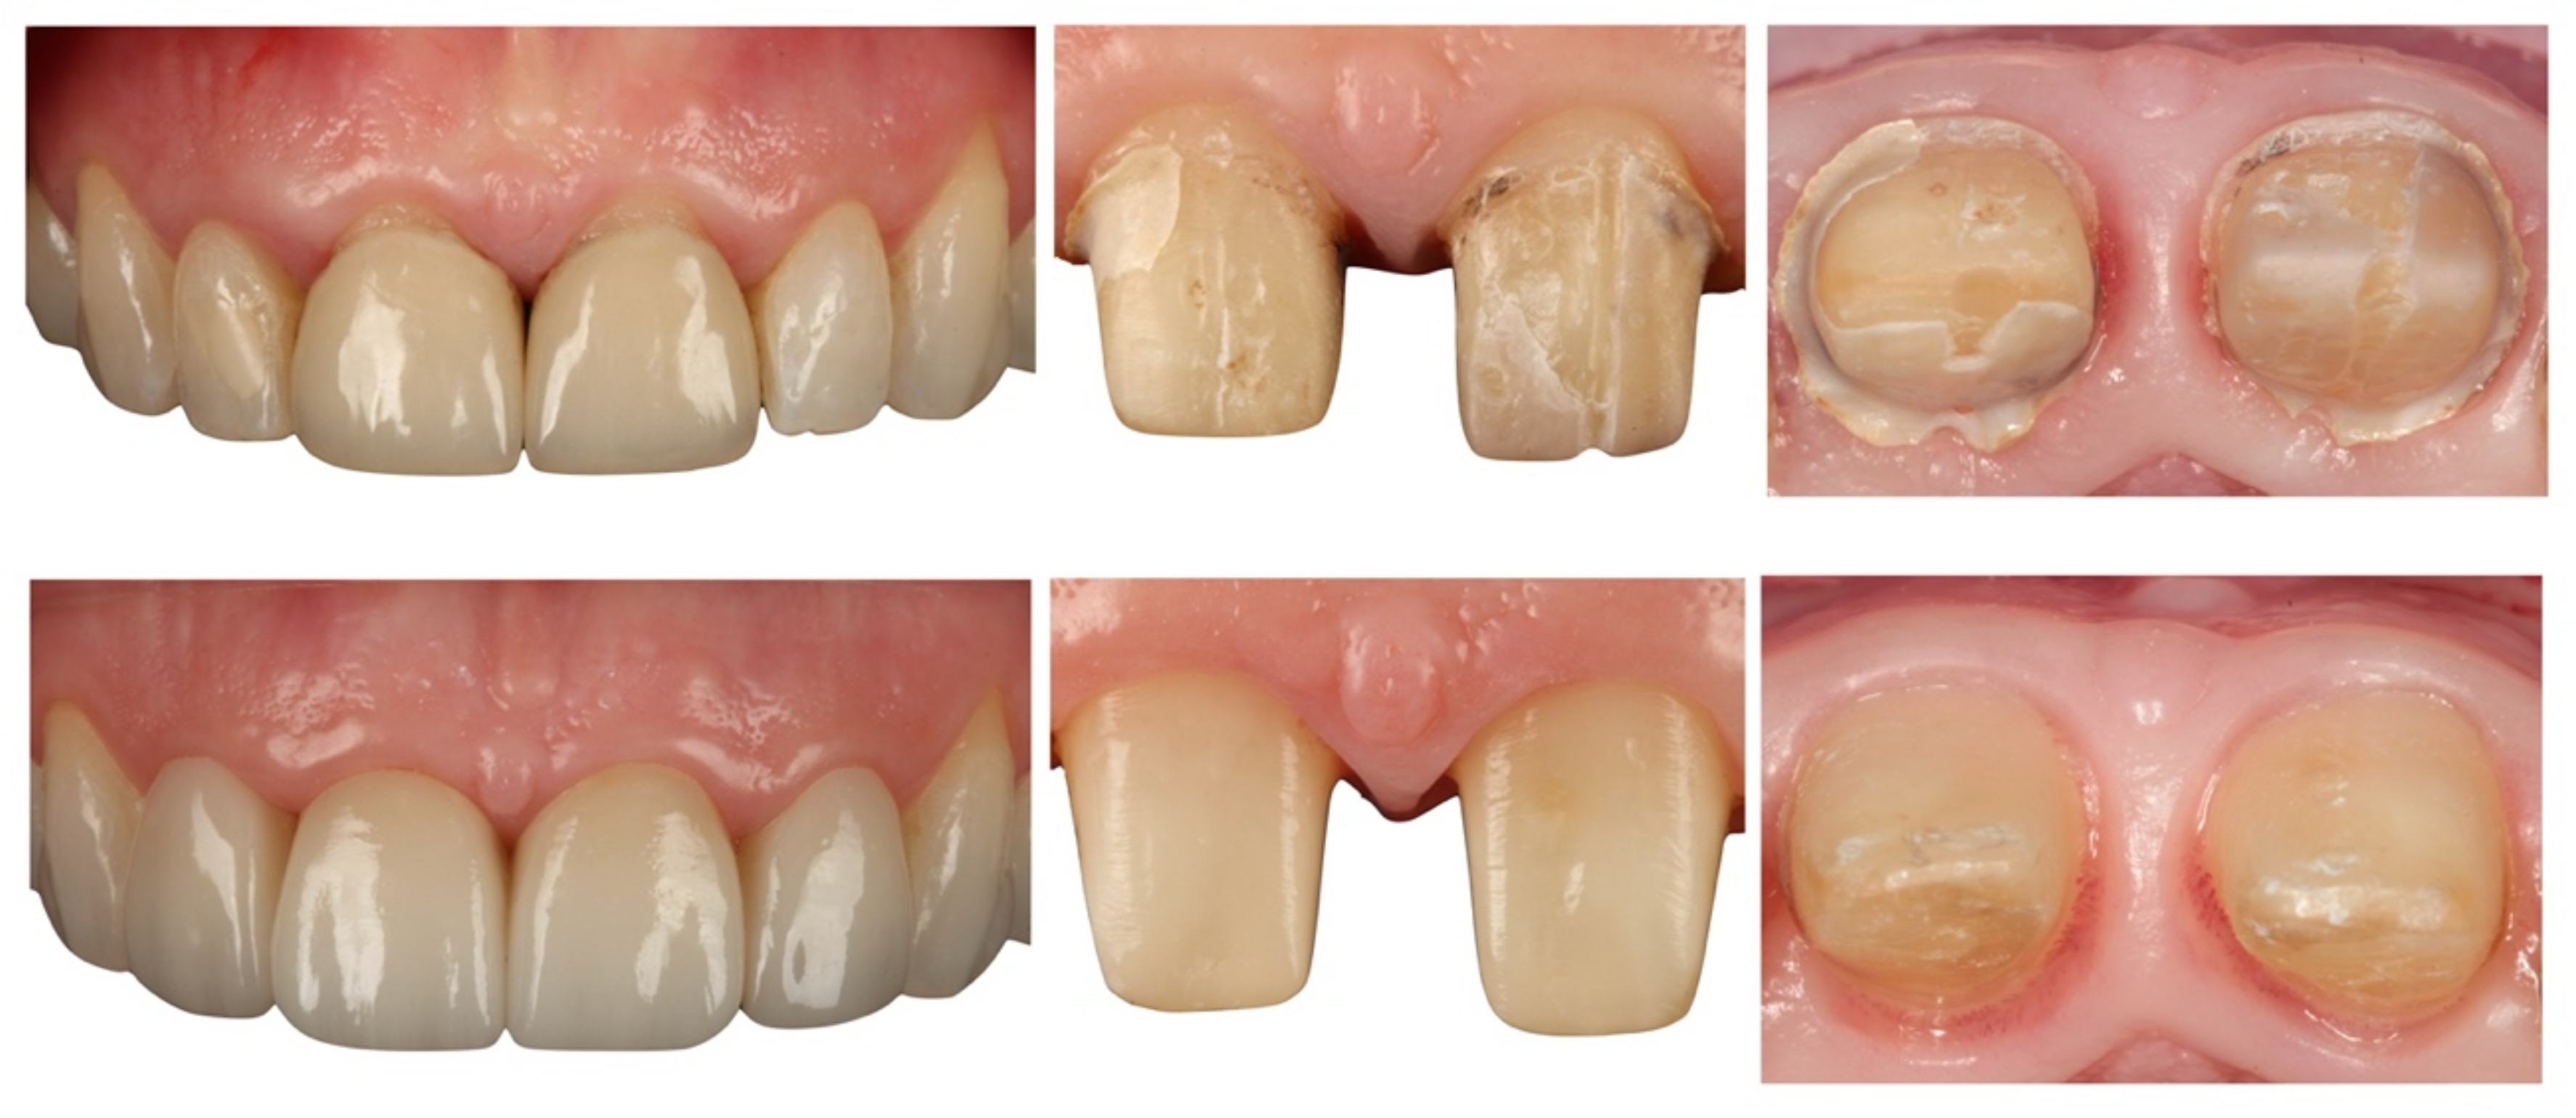

- Teeth treated with this technique presented improved plaque indices, stable probing depths, increased gingival thickness, and stable gingival margins over the 6-year follow-up.

- Treatment with a fixed prosthesis using the BOPT technique has a positive impact on patient satisfaction, especially in cases concerning the re-treatment of old fixed prostheses. This fact is due to the esthetic improvement not only of the restoration but also of the surrounding tissues, as it improves gingival quality by thickening the tissue, thus preventing gingival recession.

- Agustín-Panadero, R.; Solá-Ruíz, M.F. Vertical preparation for fixed prosthesis rehabilitation in the anterior sector. J. Prosthet. Dent. 2015, 114, 474–478. [Google Scholar] [CrossRef] [PubMed]

- Agustín-Panadero, R.; Serra-Pastor, B.; Fons-Font, A.; Solá-Ruíz, M.F. Prospective Clinical Study of Zirconia Full-coverage Restorations on Teeth Prepared with Biologically Oriented Preparation Technique on Gingival Health: Results After Two-year Follow-up. Oper. Dent. 2018, 43, 482–487. [Google Scholar] [CrossRef] [PubMed]